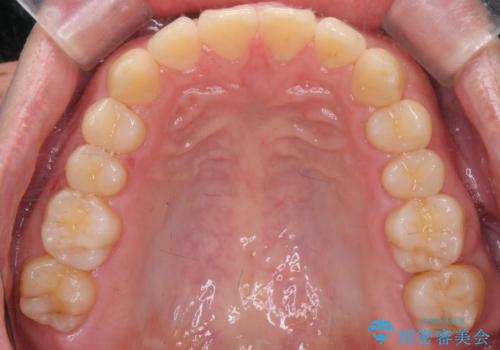

下の歯のがたつきが気になる。 インビザラン&ワイヤー部分矯正併用

- インビザラインモデレート 部分矯正

左上の奥歯がシザーバイトがありワイヤーで部分的な矯正を行い、シザーバイトを改善した後にインビザラインで全体的な矯正治療を行いました。

歯のがたつきが改善され大変満足されました。